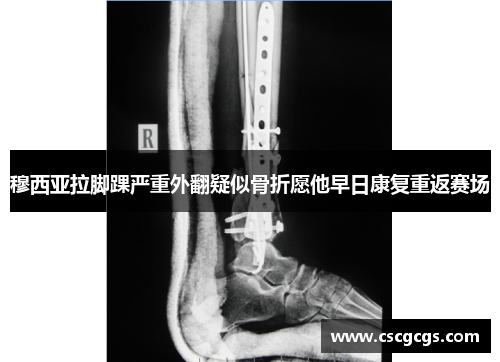

穆西亚拉在比赛中的脚踝严重外翻,首先引发了球迷们的极大关注。从现场画面来看,穆西亚拉在与对手的对抗中,脚踝不幸扭曲并发生了外翻。伤势的严重程度随即被专家判断为疑似骨折,这无疑让人担忧。这种外翻伤害常常伴随着软组织的损伤和骨折,恢复时间相对较长。为了确保穆西亚拉能够彻底康复,医生需要对伤情做出精确评估,可能需要进行一系列的影像学检查,如X光、CT或MRI扫描,进一步确认骨折的程度和范围。

从伤情表现来看,穆西亚拉当时疼痛难忍,并且无法继续站立,明显的肿胀和淤血也表明伤势相当严重。脚踝外翻通常会造成韧带和肌腱的损伤,若伴随骨折,将增加恢复难度。即便伤势最终确认为骨折,术后治疗和康复的过程也将是漫长的,需要精心的护理和合理的运动计划。